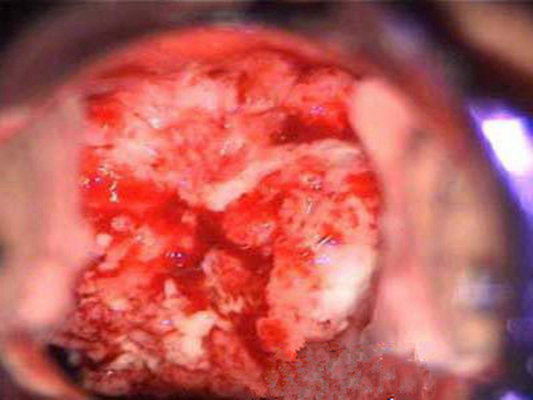

子宮頸糜爛圖片

宮頸糜爛 (8)

宮頸糜爛 (9)

宮頸糜爛 (56)

宮頸糜爛 (57)

宮頸糜爛 (58)

宮頸糜爛 (59)

宮頸糜爛 (6)

宮頸糜爛 (60)

宮頸糜爛 (7)